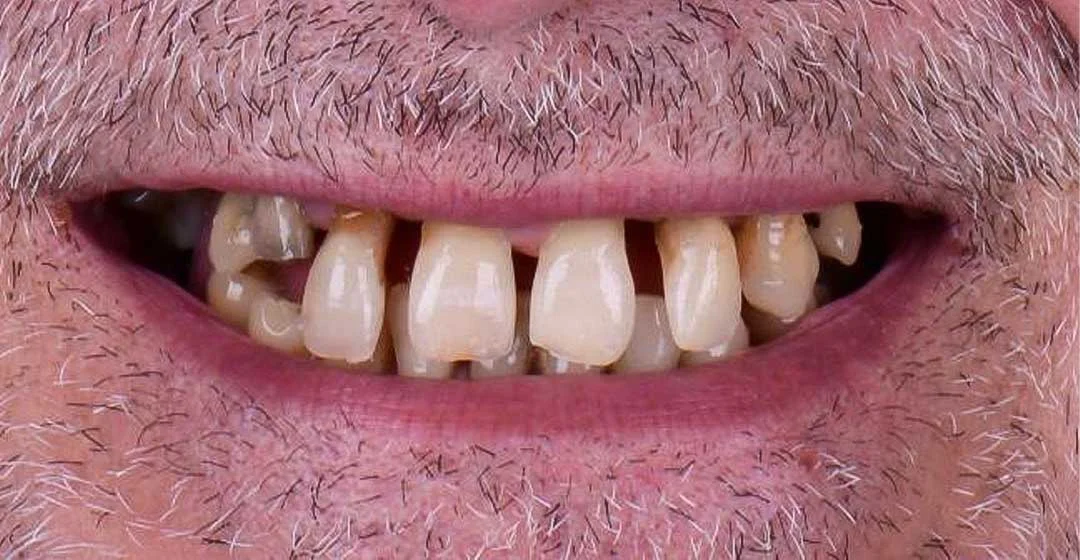

Real full mouth rehabilitation and graftless implant cases treated by Dr Nabeel.

Best for multiple missing teeth or loose dentures. We place implants in stronger bone areas and give fixed teeth for suitable cases. Local anesthesia keeps you comfortable during treatment.

Many patients think they must do bone grafting first. Some cases can avoid that with graftless implants. You get a safety first plan, comfort focused treatment, and a clear timeline. Every case is different, so we confirm suitability with a 3D scan before treatment.